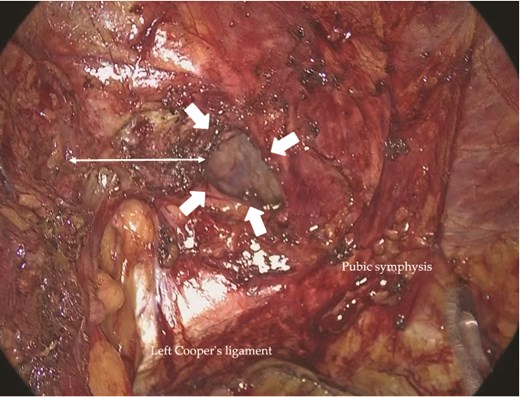

On the left, the recurrent hernia orifice was identified adjacent to one of the mesh plugs, with the pseudosac firmly adherent to the plug (Fig. 5). After careful sharp and blunt dissection, a recurrent orifice was clearly exposed in the left pubic region and classified as R1M2 (Fig. 6). A circumferential margin of ~2.5 cm was secured around the defect. The laterally placed plug did not interfere with the repair and was left in situ. A 15 × 10 cm self-gripping mesh (ProGrip™) was placed to cover the recurrent defect with a 2.5 cm margin and was supplemented with tacker fixation because overlap was limited (Fig. 7). Although the left-sided mesh covered the right hernia orifice, overlap on the right was insufficient (Fig. 8), so an additional mesh was applied for reinforcement. The right-sided high peritoneal incision was sutured and closed in a standard fashion (Fig. 9). The postoperative course was uneventful. At 5-month follow-up, there was no clinical evidence of recurrence.

Intraoperative view of the left inguinal region. An R1M2-type recurrent hernia orifice (arrows) was identified adjacent to a mesh plug. A circumferential margin of ~2.5 cm (double-headed arrow) was secured around the defect.